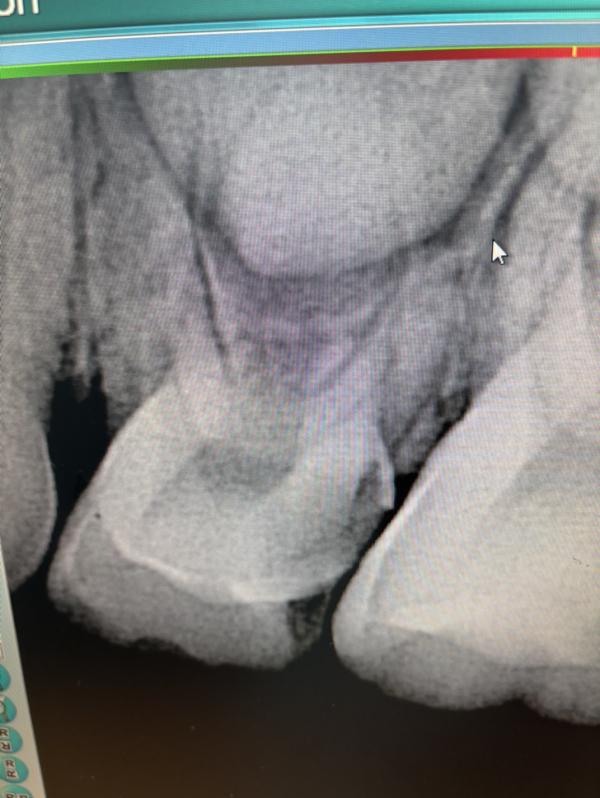

За или против лечение маляра молочного ?

Корни,вроде,еще не рассосались, надо лечить

@dusel, тогда бы не трогала. Скоро смена. Корни рассасываются